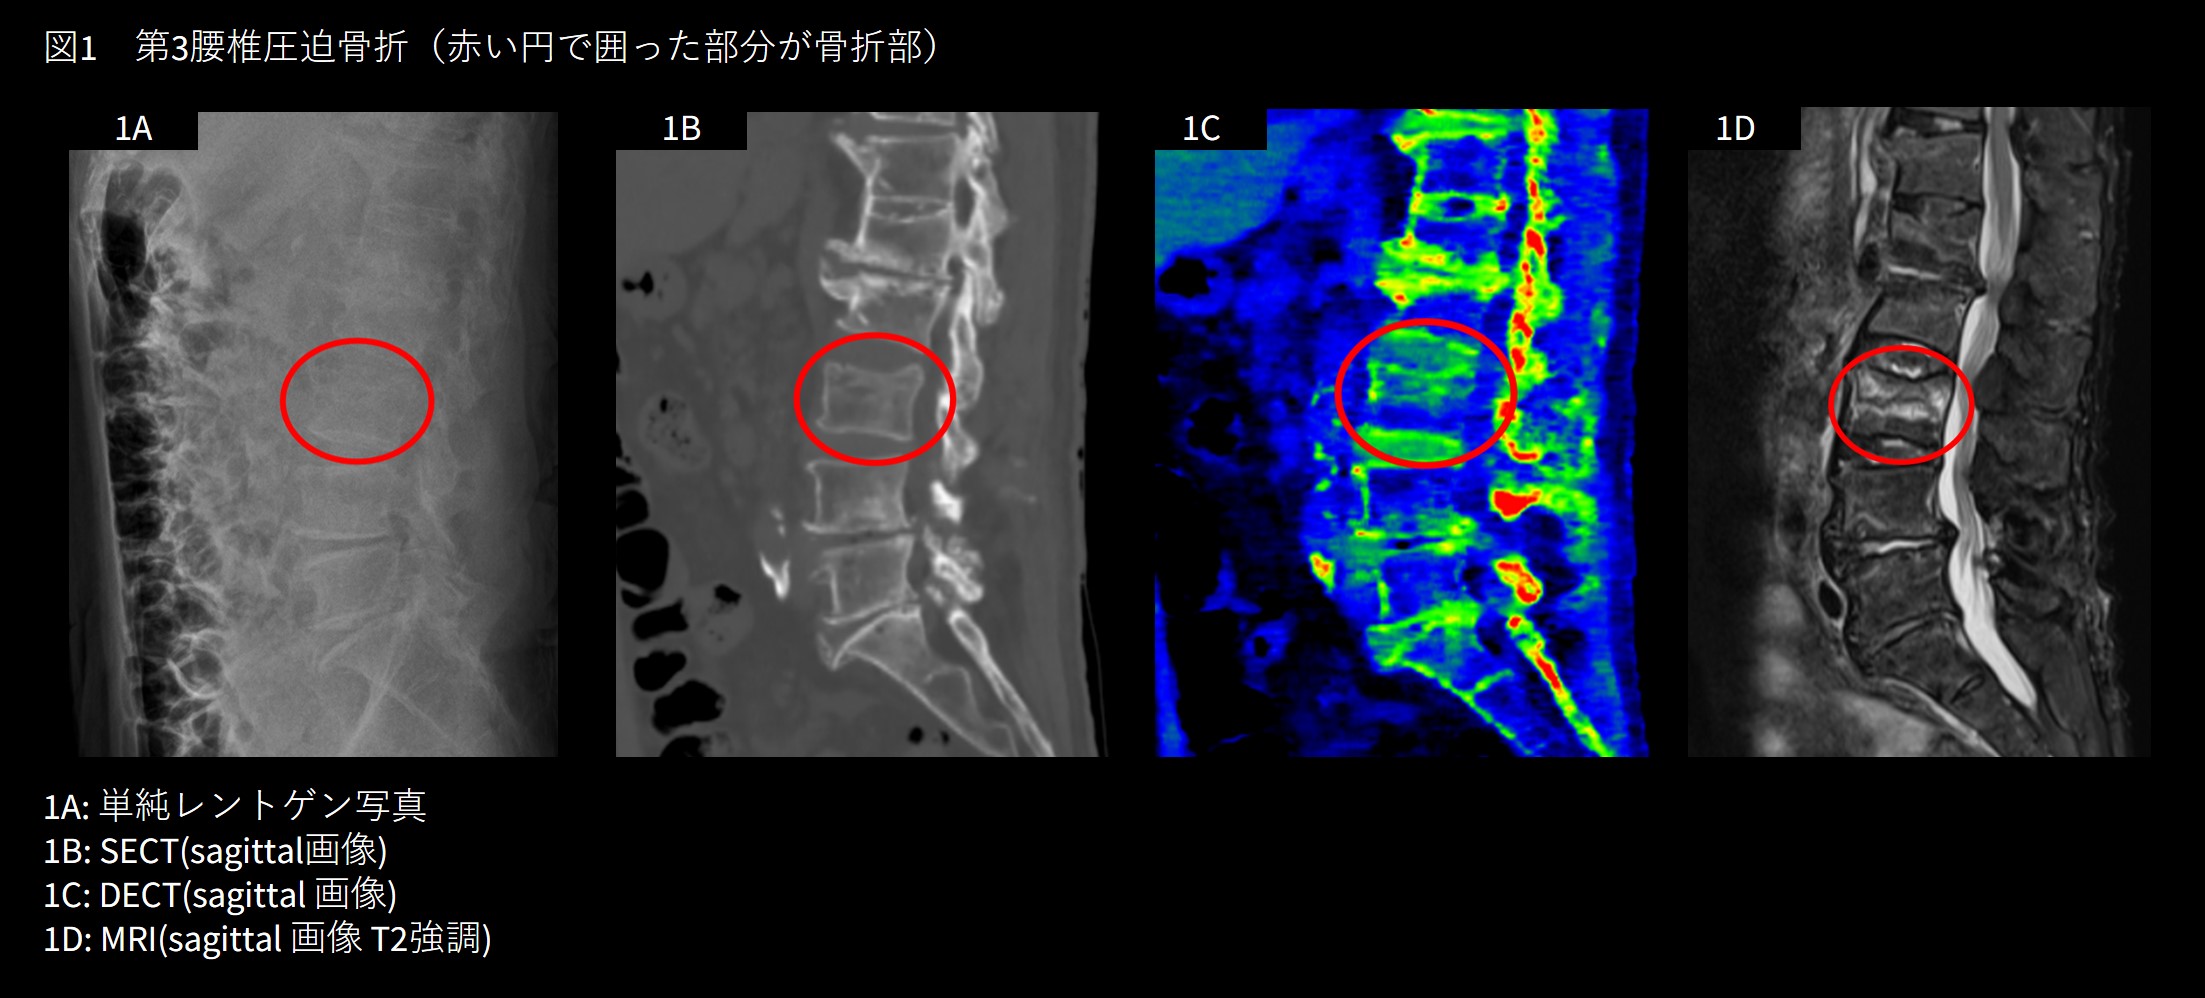

胸腰椎圧迫骨折は骨粗鬆症が基盤にあり、転倒などで容易に発生する脆弱性骨折の一つである。急性期には体幹固定装具を装着する必要があり、また症例によっては経皮的椎体形成術(Balloon Kyphoplasty; BKP)の適応がある。したがって、その骨折が新規骨折か否かを迅速に判断することが重要である。従来はMRIを撮像しないと診断は困難であったが、DECTを活用することでその診断が可能となる。新規骨折の場合、DECTでは骨折による出血が骨髄内に水の高密度領域として描出される(図1)。陳旧例では骨髄内の水密度変化は描出されないため、新規骨折か否かの診断が容易となる。

RevolutionApexElite_Nishinomiya02.jpg